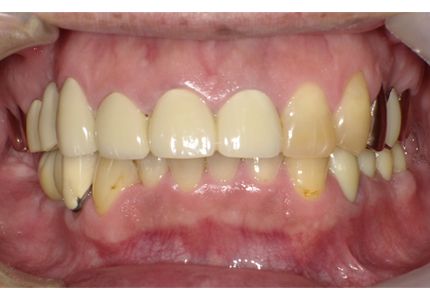

患者:Y.S 様

初診日 :2018年10月

主訴 :上顎前歯部審美障害、臼歯部補綴治療

1.初診時口腔内写真(2018年10月)